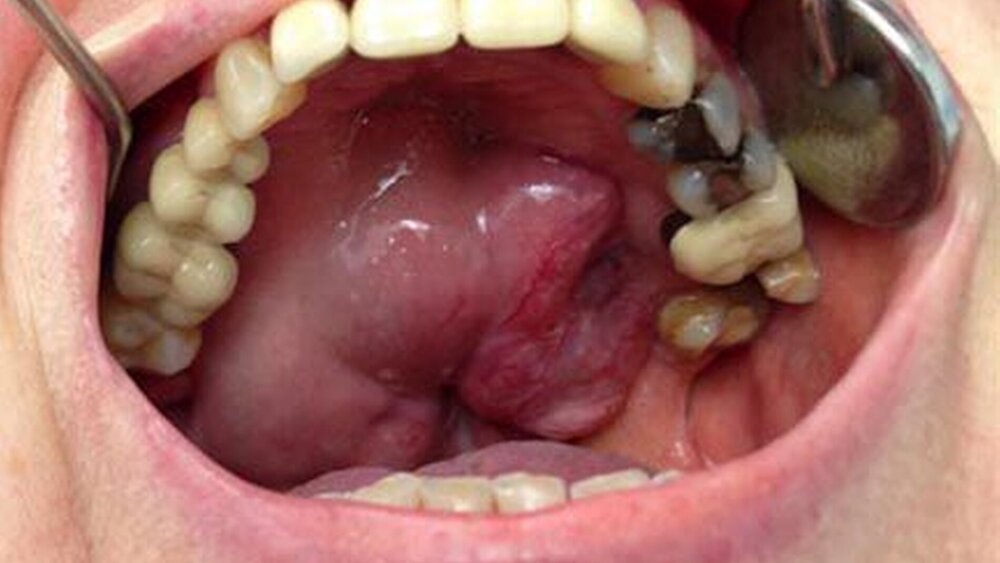

Die Frau stellte sich mit einer großen intraoralen harten, nicht ulcerierenden Vorwölbung des Gaumendachs vor. Sie gab an, bereits vor circa 30 Jahren sei die Diagnose eines kleinen, gutartigen Speicheldrüsentumors im Bereich des harten Gaumens durch eine Gewebeprobe gestellt worden. Damals hatte sie jegliche Therapieoptionen verweigert und auf ein abwartendes Verhalten bestanden.

Mittlerweile war der Tumor verdrängend nach kranial bis in die Nasenhaupthöhle und nach kaudal in die Mundhöhle teilweise bis auf das Niveau der Okklussionsebene gewachsen. Der extraorale Befund war gänzlich unauffällig.

Die computertomografische Bildgebung zeigte eine inhomogene, kontrastmittelanreichernde und mittellinienüberschreitende Raumforderung im Bereich des Gaumens, die kaudal in die Mundhöhle und kranial in das Cavum nasi reichte. Die Größenausdehnung betrug circa axial 67 x 56 x kraniokaudal 52 mm.